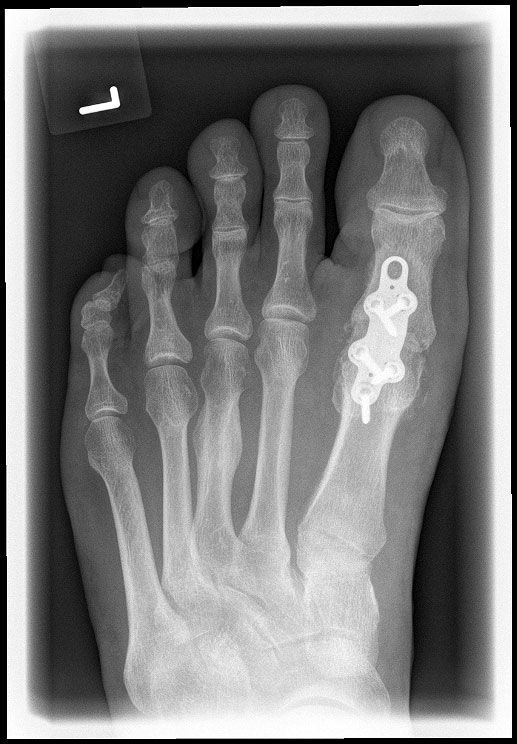

Das nachfolgend präsentierte OP-Verfahren zeigt die Großzehengrundgelenkarthrodese mit Gelenkflächenpräparation mittels sogennanter „Cup-and-Cone“-Fräsen und einer dorsal angebrachten variablen winkelstabilen Platte mit Gleit-/Kompressionsloch.

Durch die Verwendung sogenannter „Cup-and-Cone“-Fräsen und die Osteosynthese mit winkelstabiler Platte ggf. in Kombination mit einer interfragmentären Zugschraube kann die Rate der Pseudarthrosen vor allem bei schlechten Knochenverhältnissen deutlich reduziert werden, sodass dieses Verfahren zunehmend empfohlen wird 9.

• Röntgen-Kontrolle der Osteosynthese und Stellung intraoperativ / postoperativ, nach 3 Wochen und nach 6 Wochen